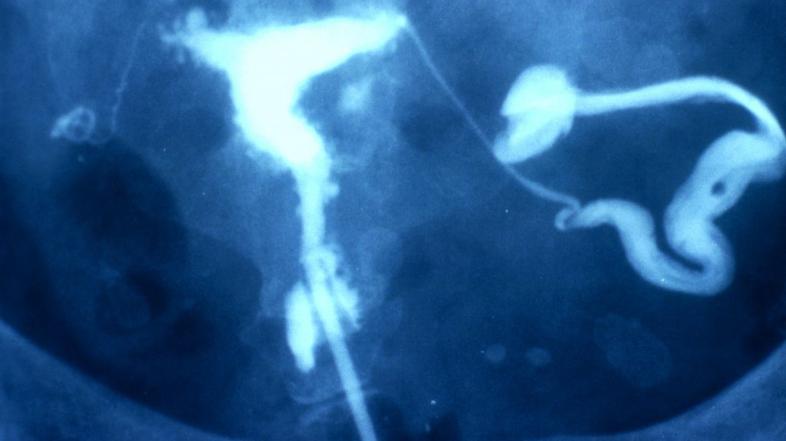

Endometrioza je pojav tkiva s histološkimi in funkcionalnimi značilnostmi endometrija (sluznice maternice) zunaj maternične votline. Tako kot v maternici je tudi tkivo endometrioze podvrženo hormonskim spremembam, zato se tudi zunaj nje odebeli, odlušči, zakrvavi, vendar ne more odtekati, ker nima izhoda. To povzroča zarastline, izrastke, lezije, ciste in lokalna vnetja, ki lahko povzročajo močne bolečine. V primeru cist obstaja nevarnost, da te počijo in pride do razsoja celic po drugih organih.